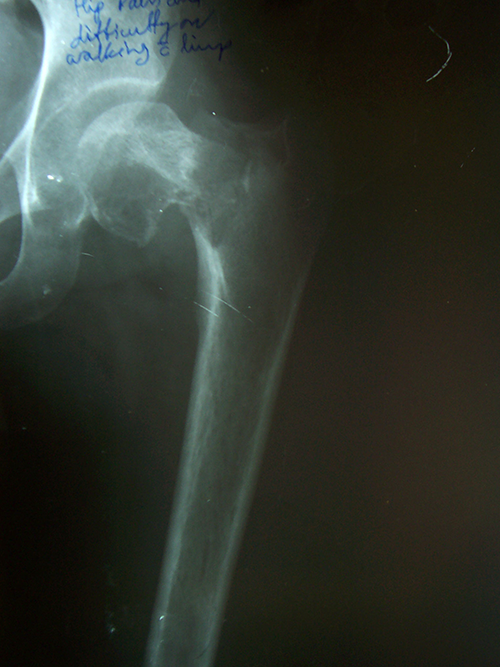

Case:3 Septic Arthritis-THR

2Months Pre-Op

Imm Post-Op

Total Hip Replacement